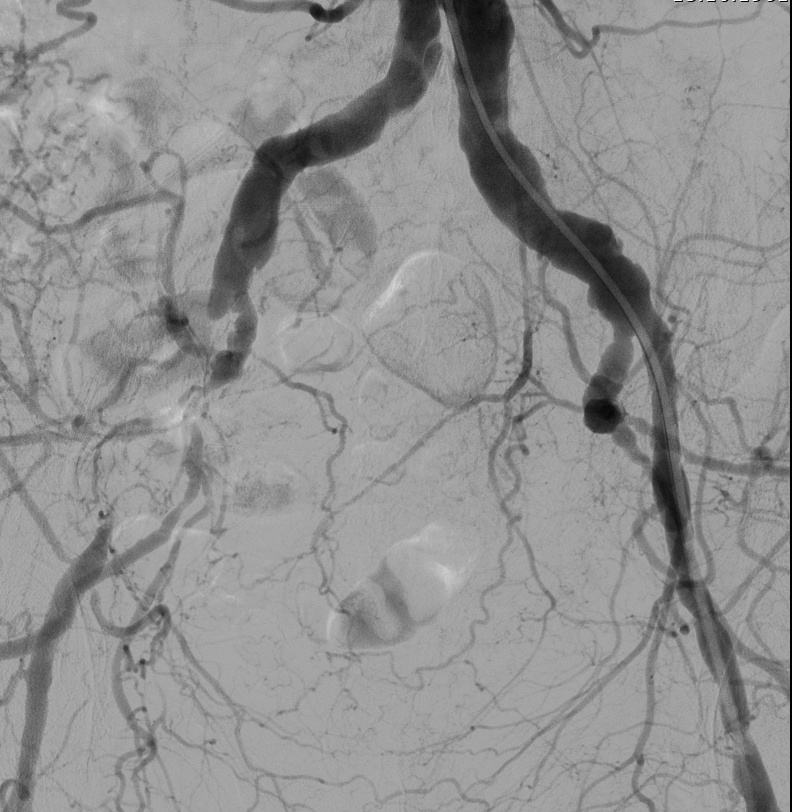

— Вчера мы с Виктором Анатольевичем Егоровым сделали показательную операцию, — рассказывает заведующий отделением рентгенэндоваскулярных методов диагностики и лечения Павел Антонович Алимов. — У пациента была патология терминального отдела аорты с преимущественным поражением левой подвздошной артерии. Поставили один стент. Всё.

За этой краткостью — огромный путь, который прошла сосудистая хирургия. Ещё недавно такому пациенту делали бы полостную операцию: долгий наркоз, большой разрез, недели в стационаре, месяцы реабилитации. Риск осложнений, тяжёлое послеоперационное восстановление.

— Сегодня мы можем сделать то же самое эндоваскулярно, — поясняет Алимов. — Это гораздо менее травматично, не требует сложного анестезиологического пособия, а восстановительный период — в разы короче.

В сосудистом отделении СМЦ ФМБА России выполняют как открытые операции на терминальном отделе аорты, так и эндоваскулярные вмешательства. В том числе при синдроме Лериша — тяжёлой патологии, когда сужение аорты грозит ампутацией конечностей.

Исследования подтверждают: эндоваскулярное лечение аорто-подвздошных окклюзий демонстрирует технический успех до 97,8%, а средний срок госпитализации составляет всего 2 дня. При открытых операциях эти цифры совершенно иные.